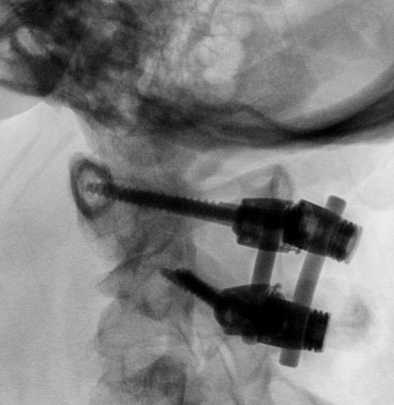

Options

Collar

Halo thoracic brace

Jefferson HTB Xray

Post reduction halo xray

Jefferson Fracture Flexion Extension Views Stabe0001Jefferson Fracture Flexion Extension Views Stabe0002

Flexion and extension views demonstrating stable Jefferson fracture post halo treatment